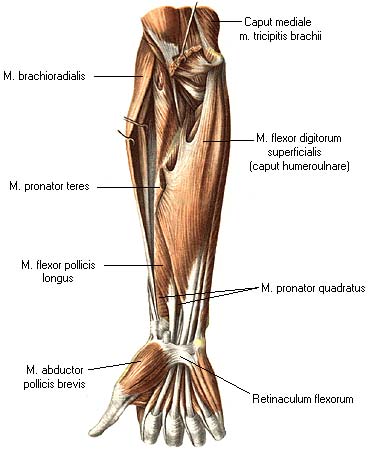

Анатомия и функции мышцы brachioradialis